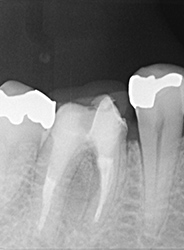

こちらのレントゲン写真を見てください。どちらかの歯医者さんで神経を取っています。根管に入れる薬は白く映ります。赤矢印部分です。一番右側が模式図ですが、青い部分が薬、根っこの先の赤点が化膿している部分です。

薬がほとんど入っていないのがわかります。黄矢印部分です。青矢印まで薬が入らないといけないのですが、全く入っていません。その結果、根っこの先が黒くなっています。膿が貯まって化膿すると黒く写ってくるのです。

別な歯科医院で治してもらいました。薬が根の先まで入っているのがわかります(黄矢印)。 根尖の黒い影が消失しています(赤矢印)。骨が再生すると白く写るようになります。

①の写真はどちらかの歯医者さんで神経を取ってもらったレントゲン写真です。根っこの中に薬が全く入っていません。

②の模式図で青く描かれている部分が薬です。

根の先を見ると小豆ぐらいの大きさの黒い影が見えます。根の中でばい菌が繫殖し感染を起こすとこのような黒い影ができます。黒い影の部分は膿(ウミ)が貯まっています。こうなると腫れて痛みが出てくるのです。

③、④の写真はそれを治した後のレントゲン写真とその模式図です。白く映っている薬が根の先まできちんと入っているのが確認できます。そして根の先にあった黒い影が消えているのが分かります。根の先の炎症が治って、骨が再生すると白く映るのです。

実はこのケース、歯医者さんの神経を取る治療でこのような根っこの病気になってしまったのです。そこでこの患者さんは神経を取った歯医者さんではなく、別の歯医者さんに受診して、根っこの治療をして治したのです。

薬が真ん中までしか入っていないため、膿が貯まっている。

薬が根尖までしっかりはいっていない。

化膿している